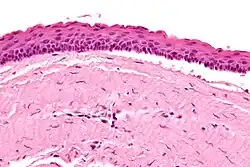

| Micrograph of an odontogenic keratocyst. H&E stain. | |

Odontogenic keratocysts have a diagnostic histological appearance. Under the microscope, OKCs vaguely resemble keratinized squamous epithelium;[15] however, they lack rete ridges and often have an artifactual separation from their basement membrane.[2]

The fibrous wall of the cyst is usually thin and uninflamed. The epithelial lining is thin with even thickness and parakeratinised with columnar cells in the basal layer which have focal reverse polarisation (nuclei are on the opposite pole of the cell).[13] The basal cells are an indication of the odontogenic origin as they resemble pre-ameloblasts. The epithelium can separate from the wall, resulting in islands of epithelium. These can go on to form 'satellite' or 'daughter' cysts, leading to an overall multilocular cyst.[10] Presence of daughter cysts is particularly seen in those with NBCCS.[13] Inflamed cysts show hyperplastic epithelium which is no longer characteristic of OKCs and can have resemblance to radicular cysts instead. Due to areas of focal inflammation, a larger biopsy is required for correct diagnosis of odontogenic keratocysts.[10]